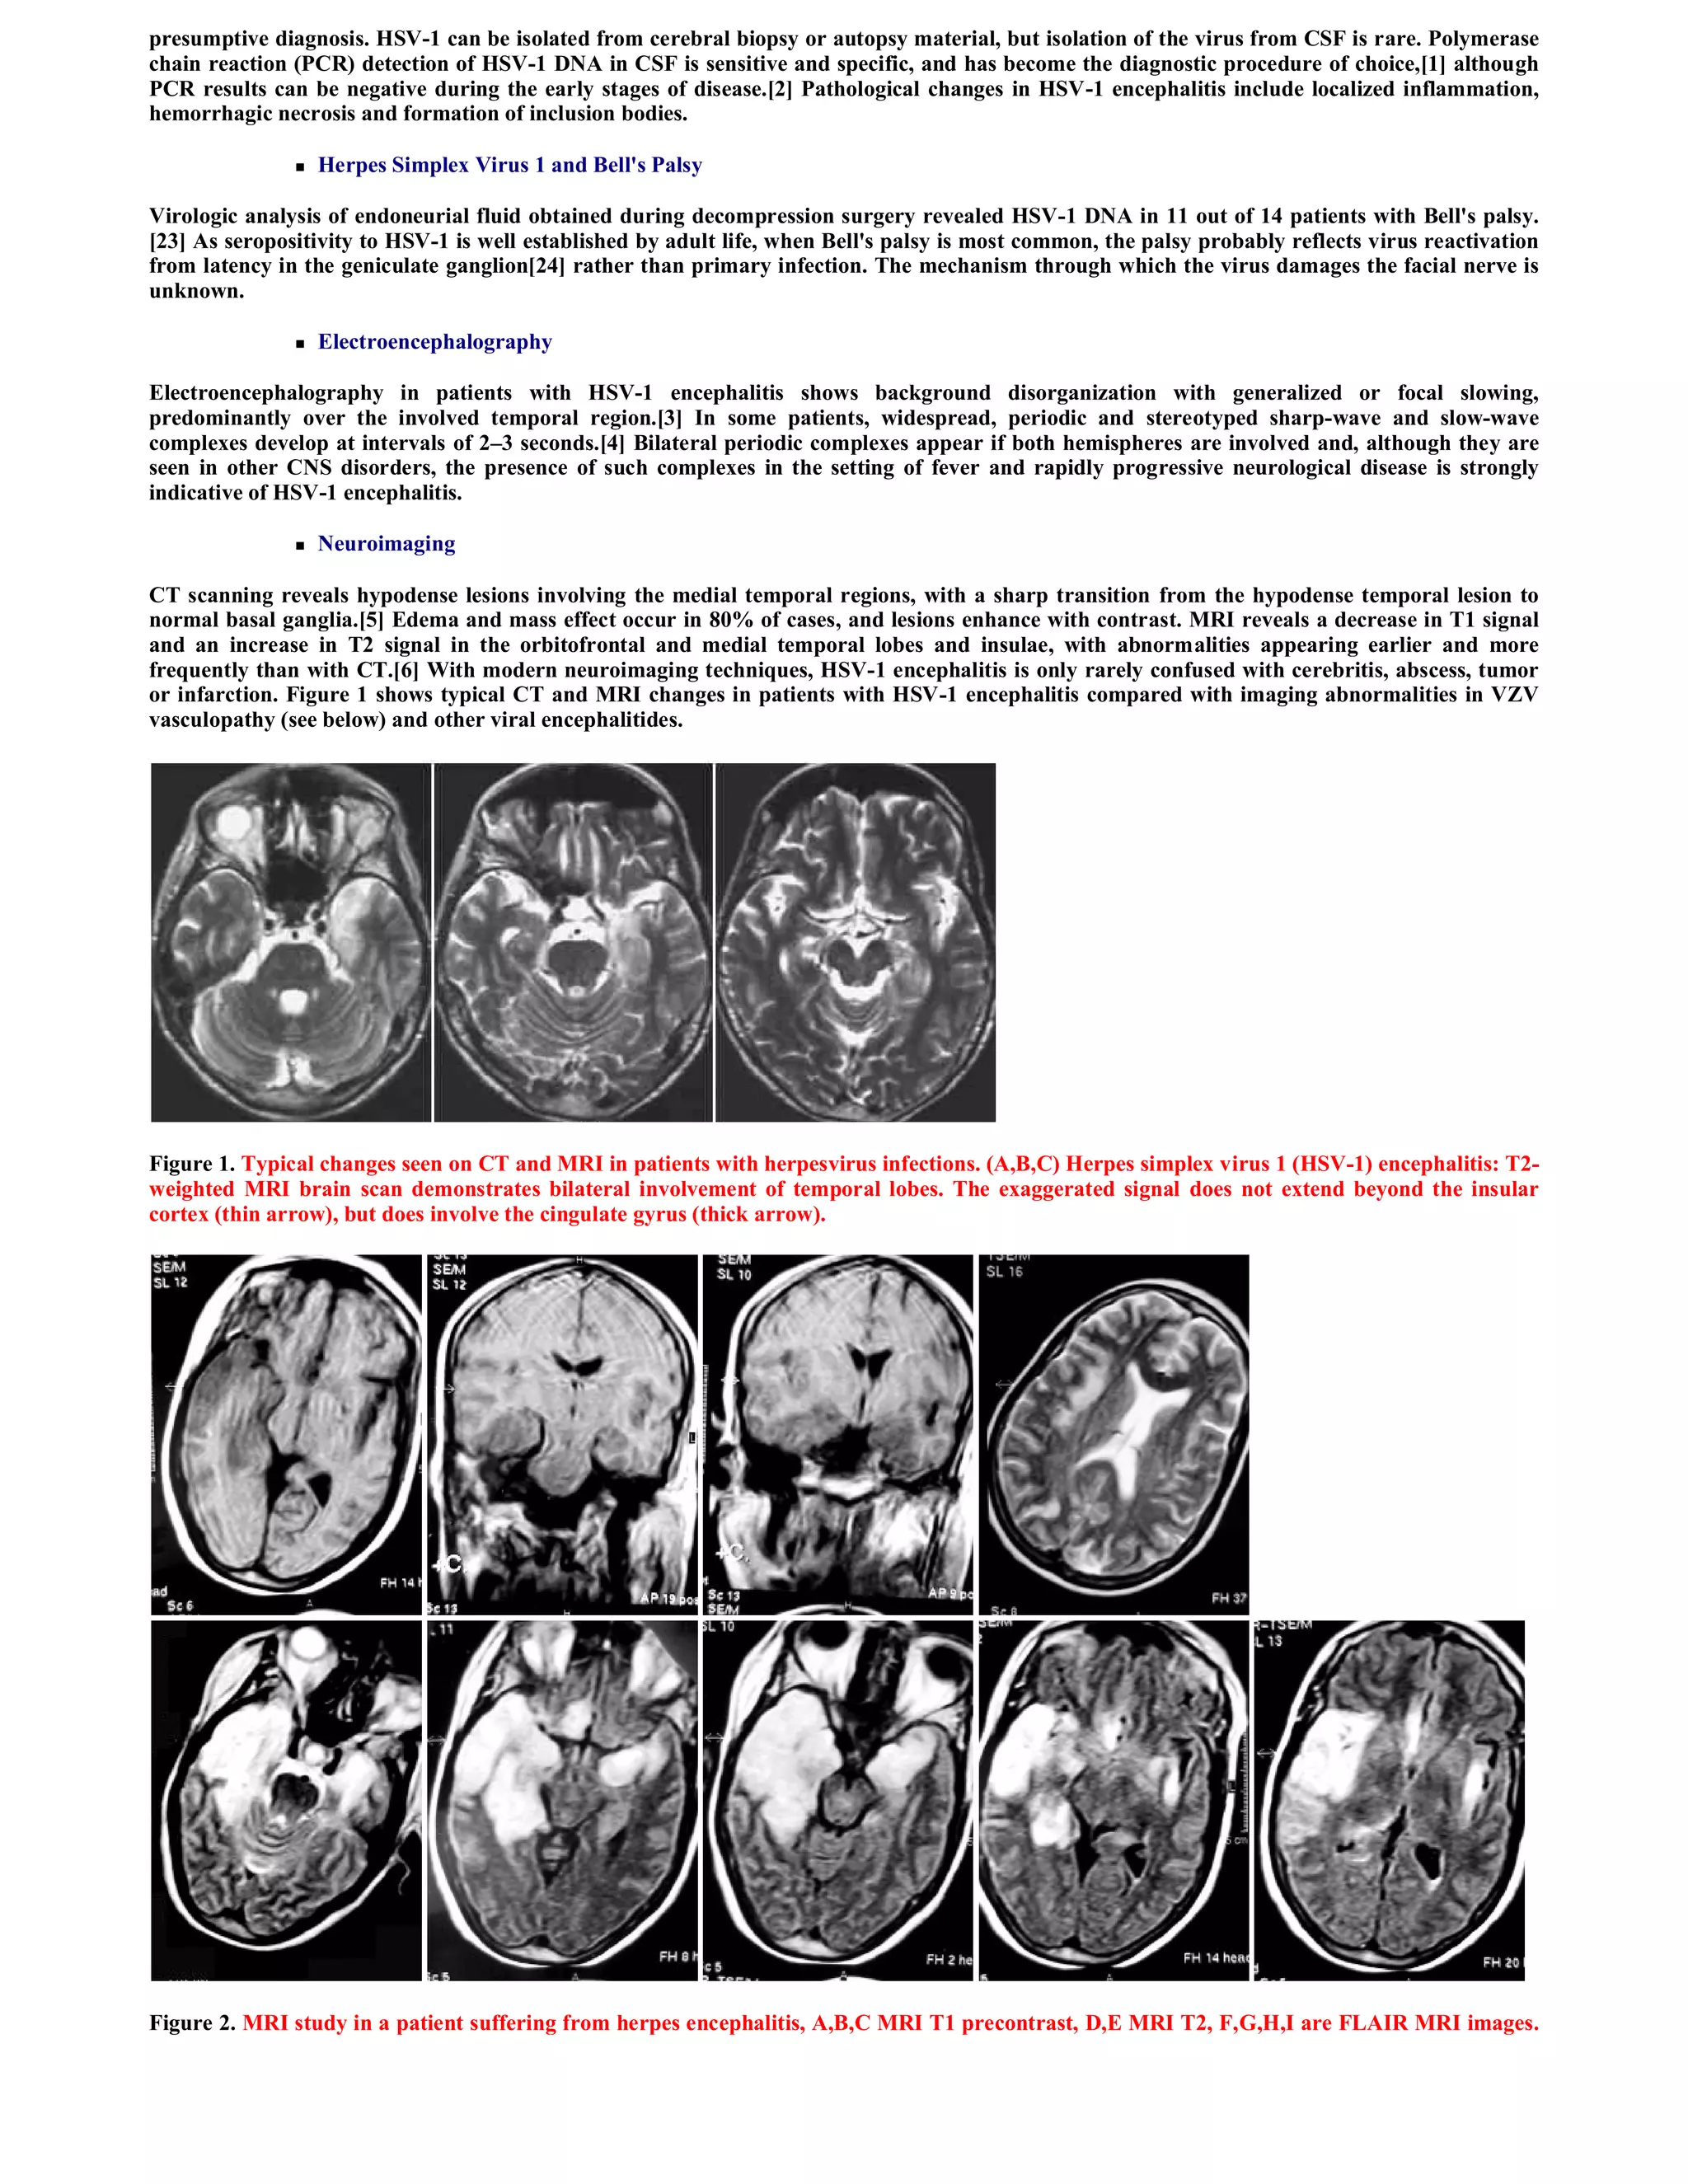

Massive brain edema is observed in most of patients. Corticosteroids are probably not useful in the treatment of edema associated with HSE.

Data from animal studies have shown even potentiation of disease. 48 Brain edema in all patients responded dramatically, even when massive, to

acyclovir It seems quite logic that treatment of the cause of brain edema is the best treatment of brain edema.

Figure 8. A case of herpes encephalitis treated with acyclovir, notice the massive brain oedema before treatment (A), also notice the gradual

reduction of brain oedema in (B) and complete resolution of brain oedema in (C) following treatment with acyclovir, this was coupled with

dramatic clinical improvement. Notice the residual frontal infarction that became apparent after resolution of the encephalitic process.